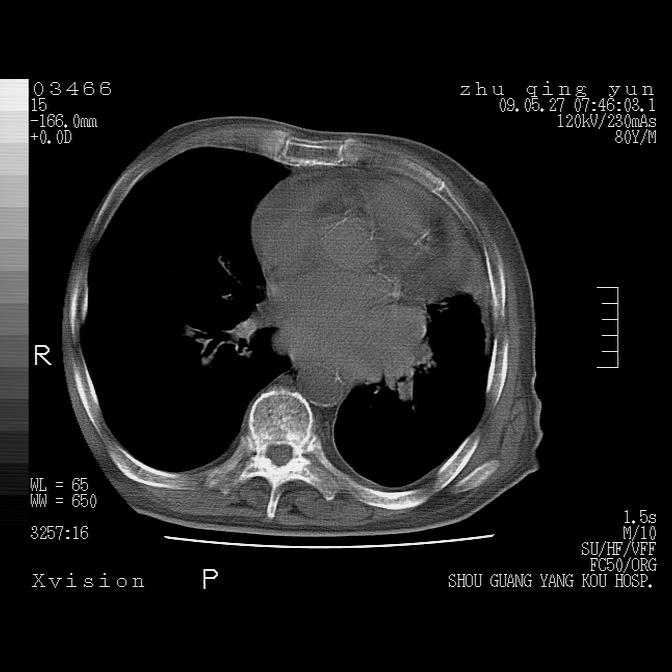

病人男性,年龄80,气喘来院,其他病史不太详细,1月前有过恶心,呕吐,在当地人民医院做过钡餐,诊断胃炎,

1)考虑左肺中央型肺癌并阻塞性肺炎,后下纵隔受侵伴纵隔淋巴结转移。2)双侧少量胸腔积液,胸膜增厚。3)心包积液。

1)考虑左肺中央型肺癌并左肺下叶阻塞性肺炎、不张;左胸膜腔积液、心包积液、纵隔淋巴结转移;癌肿累及左心房。2)左心室大。冠状动脉壁钙化斑。

1)考虑左肺中央型肺癌并左肺下叶阻塞性肺炎、不张;左胸膜腔积液、心包积液、纵隔淋巴结转移;癌肿累及左心房。

考虑左肺中央型肺癌并左肺下叶阻塞性肺炎、不张;左胸膜腔积液、心包积液、纵隔淋巴结转移;癌肿累及左心房